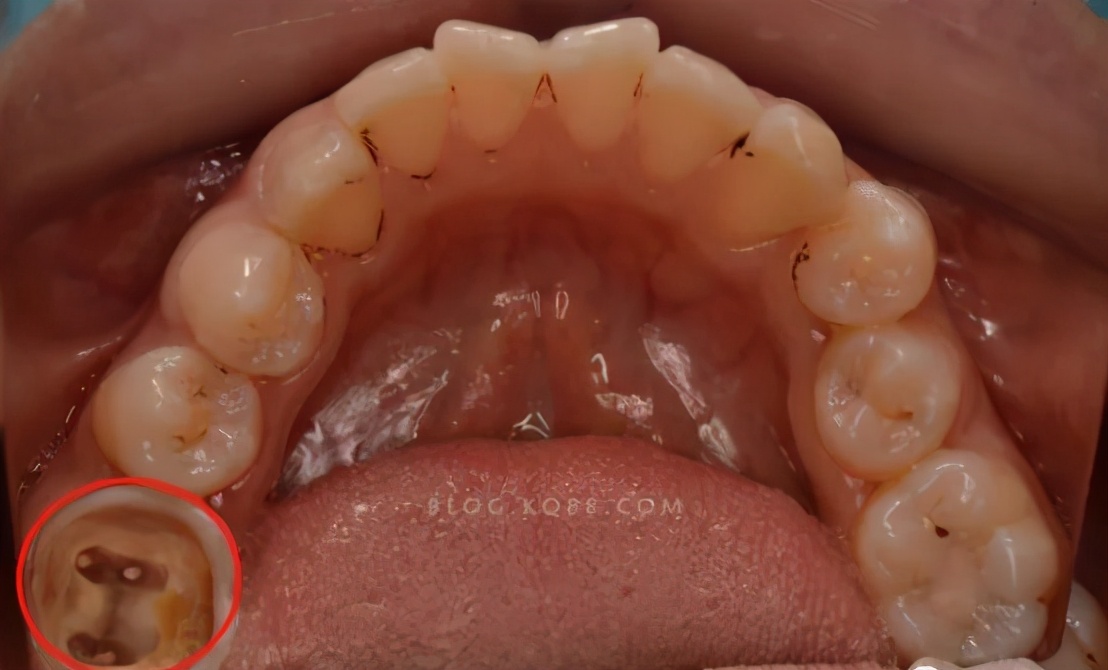

牙齿残根不疼就没事,别管它?!#雅悦齿科#

嵌体修复

如果牙龈中的根足够长,通常可以进行核后冠。

由于只剩很少的牙齿组织,为了更好地固定牙齿,牙医会将牙桩插入根管中,在行业中我们称之为“牙桩”。

有些牙根短,如果单独修理,可能无法达到预期的效果。

这时,我们还可以将其与相邻的牙齿一起修复,以形成结合的牙冠,以增加牙齿的固位力和支撑力。